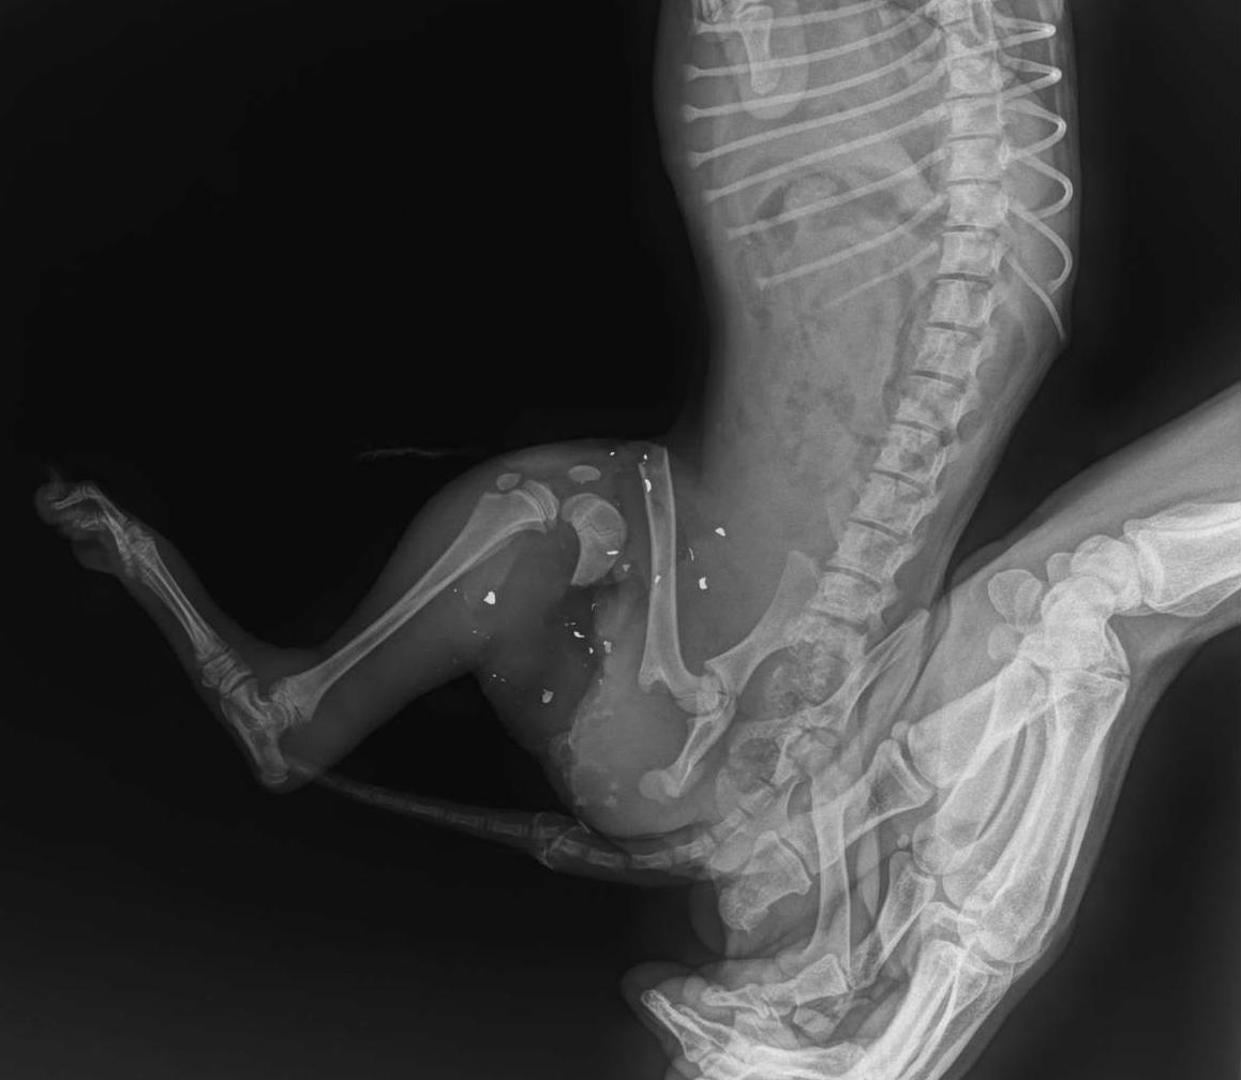

Policija traga za osobom koja je iz lovačke puške ubila tri psića, a malenu Mrvicu teško ranila zbog čega joj je amputiran rep, a u nogu ugrađena šipka

- Trenutno možemo reći samo kako intenzivno tragamo za počiniteljem - rekao nam je glasnogovornik PU vukovarsko-srijemske Domagoj Džigumović. Dodao je kako do pronalaska počinitelja ne žele izlaziti u javnost ni sa kakvim podacima. Ipak, od Donne Kovačev, koja radi u vukovarskoj veterinarskoj ambulanti Anubis klub i koja je preuzela skrb o ranjenoj Mrvici, doznajemo kako su iz njenoga tijela izvadili više komada sačme. To je i dokaz kako su psići ubijeni iz lovačke puške.

Njihova beživotna tijela pronađena su jedno do drugoga što potvrđuje i kako su ne sluteći što im se sprema došli do osobe koja je potom brutalno pucala u njih iz neposredne blizine. Mrvica je nekako preživjela ali su joj morali odstraniti polovicu repa. Strahovalo se i kako će joj radi brojnih i teških ozljeda morati biti amputirana i stražnja lijeva noga.

- U nogu smo stavili šipku i ako sve bude kako treba neće biti novih problema.Problem je što su mišići dosta oštećeni ali i što je u rani bilo svega, što smo očistili, tako da strahujemo od infekcije. Ključno je sljedećih četiri do pet dana i ako sve bude kako treba Mrvica će uskoro opet trčati i igrati se na ulici - rekla je Donna Kovačev.